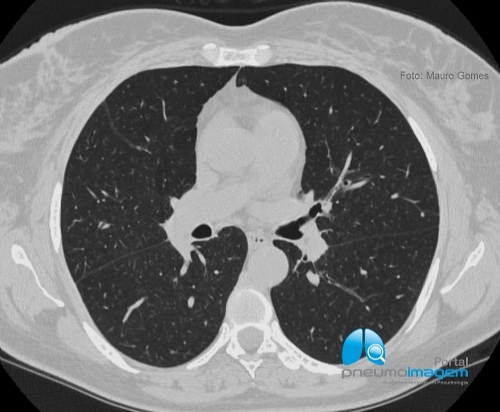

CASO CLÍNICO #46

Paciente tabagista, oligossintomático e cuja TCAR de tórax apresenta essas alterações. Qual o diagnóstico mais provável? Deixe os seus comentários abaixo.

A smoker, oligosymptomatic patient whose chest HRCT shows these changes. What is the most likely diagnosis? Write your comments below.